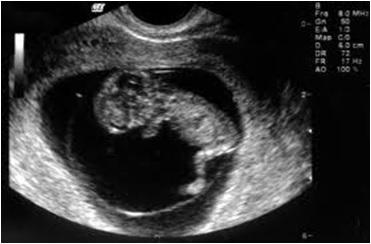

Ultrasound scans are based on ultrasound imaging and the piezoelectric effect. They are used to diagnose causes of pain, swelling, and infection in the body’s internal parts and organs. They can help in biopsies, diagnose heart conditions and assess damage after a heart attack, and are commonly used to examine babies in pregnant women.

The process involves producing sound waves to create pictures of the body’s interior. Patients lie down, and a radiologist manually moves a small probe over the body to capture real-time images.

During the scan, ultrasound waves are directed into the body and reflected by tissues. These reflected waves vary in time and intensity, and a piezoelectric crystal in the probe converts the mechanical vibrations into a varying electric current. This current helps to produce an image on the ultrasound scanner’s screen.

Since ultrasound scans don’t use radiation, they are generally considered very safe and painless.